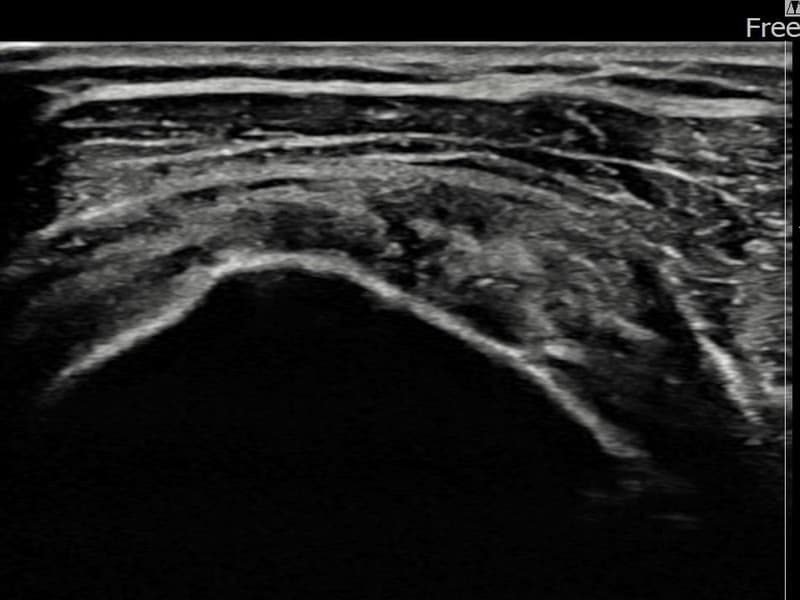

시술 전 초음파 측정 결과 파열 크기는 3.5mm × 3.1mm (부분파열)로 확인되었습니다. 시술 전 초음파에서 좌측 극상근건 관절면측의 에코 단절과 힘줄 결손 소견이 확인되었으며, 파열 크기는 3.5mm×3.1mm로 측정되었습니다. 시술 후 초음파에서 파열 부위가 재생 조직으로 채워지고 힘줄 에코 패턴이 개선된 것이 관찰되었습니다.

50대 후반 여성 환자분으로, 왼쪽 어깨 통증이 수개월 지속되어 내원하셨습니다. 초음파 정밀 검사에서 극상근건 관절면측 부분파열이 확인되었으며, 파열 크기는 비교적 소규모이나 증상이 뚜렷하였습니다. 초음파 유도 하 축소봉합술을 시행하였고, 시술 후 단계적 재활 운동을 통해 회복을 진행하였습니다. 시술 14주 후 추적 초음파에서 파열 부위의 연속성이 회복되고 어깨 기능이 정상화된 것이 확인되어 정상 생활에 복귀하셨습니다.